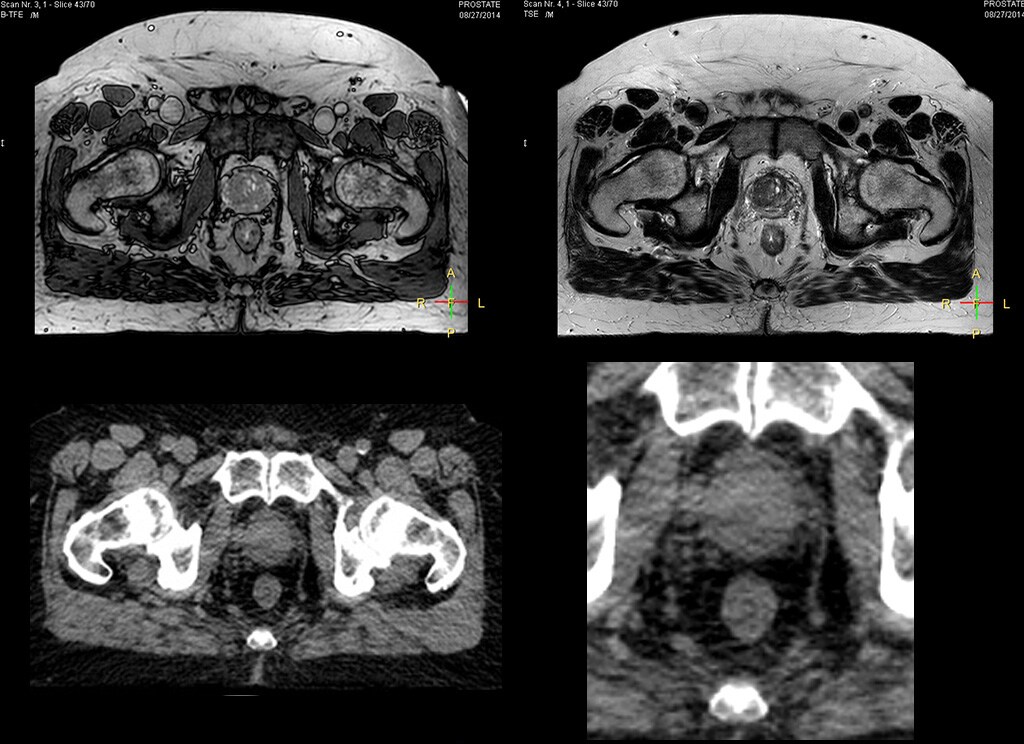

“The biggest problem for CT-based planning, especially in prostate, is you can’t see the cancer very well,” says Dr. Stevens. “On CT it can be quite challenging to see the edge of the prostate especially at the apex. When the edge of the prostate can’t be delineated well on CT, radiation oncologists will increase their margins a little bit so they don’t miss it, but that can also increase toxicity.” “Using MR, the prostate is well delineated. We quickly see the edges of cancerous tumors like in prostate cancer, and as normal structures can be defined, we can optimize the treatment plan to protect these organs and their normal function. This can potentially improve the outcome. And it improves workflow as well. We can contour more quickly, confident that the tumor is going to be in the field.” “The Ingenia 3.0T MR scanner provides high resolution allowing us to make scans fast for the patients. It also gives the potential to include methods like MR spectroscopy and diffusion weighted Imaging, which we’re in the process of doing right now,” Dr. Stevens adds.